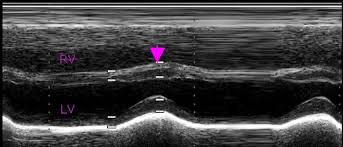

심초음파: 우심방/우심실 커짐, 우심실의 paradoxical motion (m-mode 에서 수축기에 중격이 전방으로 움직이는 움직임), 도플러로 단락 혈류 확인